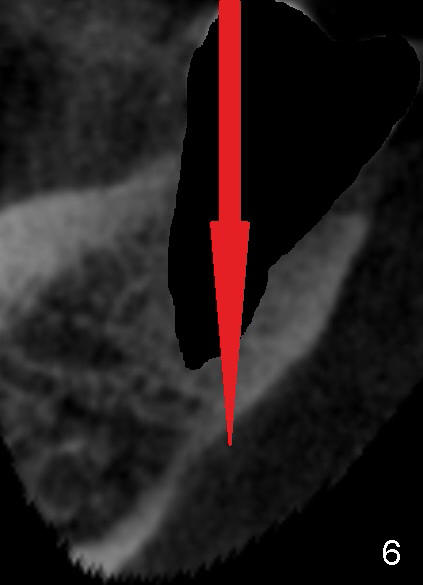

Fig.5 is an illustration, showing the socket after extraction (from Fig.1). The red circle in Fig.5 represents the lingual artery, which is the 2nd branch from the external carotid artery. When the lingual artery is severed by an overdrilling bur, it shrinks toward the external carotid artery. Hemostasis is difficult to achieve without emergency surgery. Failure to recognize the proximity of the lingual concavity may lead to perforation of the lingual plate while osteotomy is forming (Fig.6 red arrow) and potentially damage the lingual artery in the submandibular fossa. Although CBCT is essential for recognition of this special anatomy, a surgical technique is the most critical step to avoid the injury. That is to use two fingers (Fig.7 blue circles) to hold the buccal and lingual plates as low as possible and let the tactile sense guide you and keep the osteotomy in the middle of the ridge (pink arrow). One of the fingers may sense the vibration before perforation of the lingual plate. Use a long explorer to probe the osteotomy site after each bur. A surgical stent is also helpful. If an immediate implant is placed, the osteotomy should be initiated in the buccal wall of the socket of the 2nd molar (Fig.7). For the 1st molar of this case, the osteotomy is to be placed slightly lingual (Fig.8 (an illustration from Fig.2) pink arrow), since the buccal bone is lower than the lingual (Fig.2 <) and especially on the affected side (root fracture) (Fig.3).